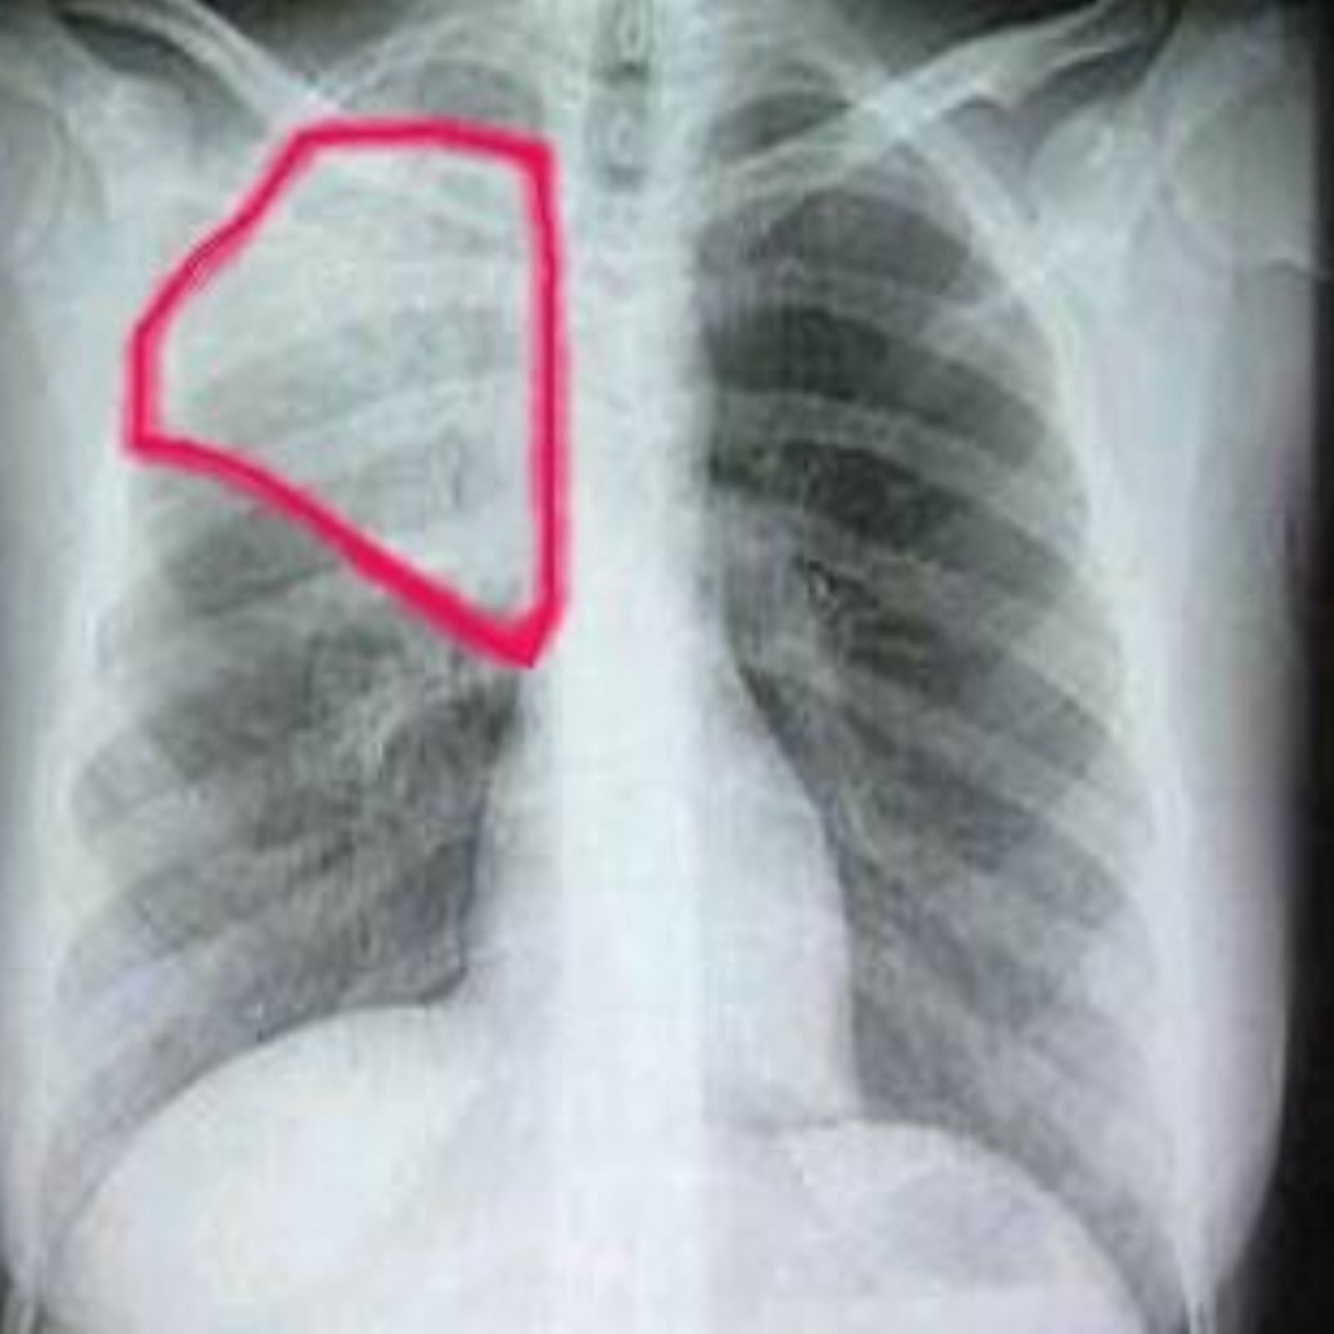

25

derrame pleural

26